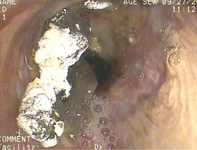

Acute aspiration

Lipoid pneumonia. A 77-year-old woman with dysphagia and achalasia following a stroke presented with recurrent lung infiltrates, including a persisting right middle lobe lesion. Hounsfield units (HU) measurement was -157, consistent with lipoid pneumonia. Comparative subcutaneous fat and aorta (blood/tissue) HU are shown

From the collection of Dr Augustine Lee, used with permission of Mayo Foundation for Medical Education and Research, all rights reserved